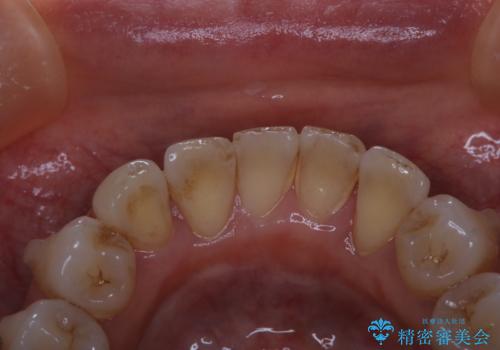

- 矯正治療前にホワイトニングがしたいとのことで来院されました。

処置前クリーニングとオフィスホワイトニングのエクセレントコースを行いました。

処置前クリーニングとオフィスホワイトニングのエクセレントコースを1回行いました。

この患者様は、歯科矯正に1、2年かかり矯正中はホワイトニングをすることが出来ないため、歯を白くしてから矯正治療にすすみたいとのことでオフィスホワイトニングを行いました。1回の施術で2.3トーン白くなり、とても白くなりました。ホワイトニングは何度も重ねて白くしていくのですが、1度で満足のいく色見になったため一旦様子を見ることにしました。